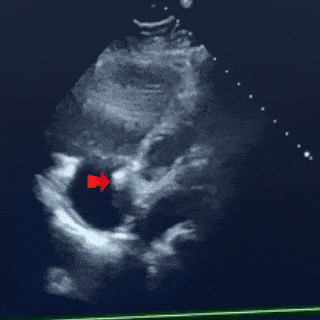

术中超声复测

主动脉短轴切面

缺损12.1mm

合并房间隔膨出瘤

缺损+房间隔膨出瘤23.0mm